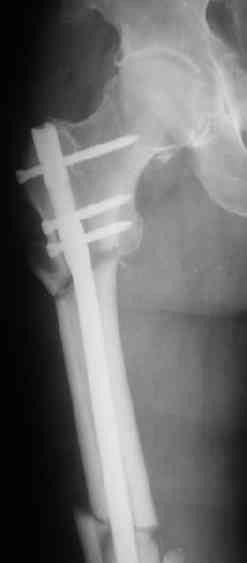

СМ> Если имеются под рукой Р-снимки, продемонстрируйте, плиз.

Вот несколько. С тисками и трубой на днях сделаем.